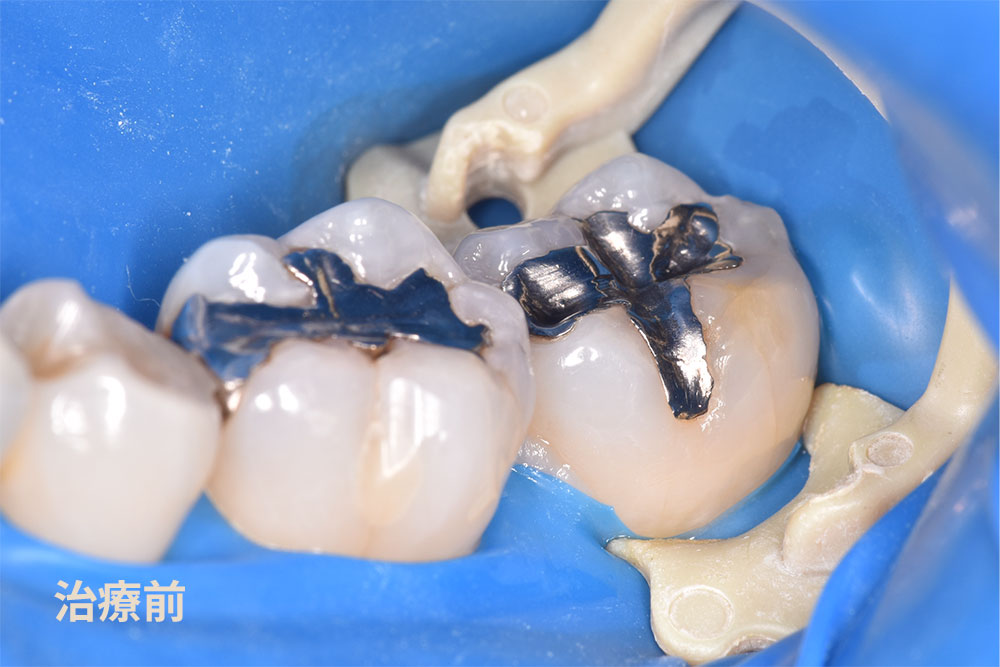

30代女性で銀歯を白い歯にしたいとのことでご来院されました。銀歯で治療されている歯は5箇所ありました。ご本人はいつ治療をしたか覚えていらっしゃらないくらい治療をしてから期間が経過していました。今回は銀歯の範囲に応じて、小さな箇所にダイレクトボンド治療、銀歯の大きな箇所(隣の歯と接している)へはセラミックインレー治療を適用できる判断し、治療を開始しました。

上の写真の茶色の箇所が虫歯でした(赤い矢印)。銀歯の隙間から新たに虫歯になっていました。マイクロスコープを用いて虫歯を的確に除去しました。写真で見ていただいている歯を取り囲むブルーの部分は、ラバーダム防湿と言います。

このラバーダム防湿を使用する理由は、お口の唾液などから湿度を減らし接着剤の効能を向上させるために当院では使用しております。ダイレクトボンディング治療は、治療の名称にも使われている直接(ダイレクト)に歯に接着剤を介して高強度の自由診療専用歯科用レジンを接着させる治療方法です。ダイレクトボンド治療にラバーダム防湿を組み合わせることで、接着力が向上し、その結果治療した詰め物が長持ちすることに繋がります。最後に治療後の写真です

下の銀歯の治療はダイレクトボンド治療とセラミックインレー治療でそれぞれ治療した症例を供覧いただきます。

セラミックインレー治療のメインはセラミックスです。ダイレクトボンド治療との違いは、適用症例が異なります。セラミックインレー治療はダイレクトボンド治療と比べて、治療をする歯の範囲が大きくなります。今回の症例のように隣の歯に及ぶ銀歯での治療をされている場合、強度の面でセラミックインレー治療を適用します。( 黄色い矢印 )